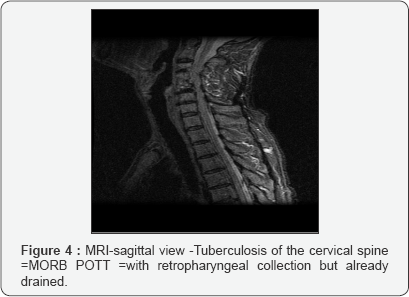

Cervical spine tuberculosis is a less common presentation but is potentially more serious because severe neurologic complications are more likely. This condition is characterized by pain and stiffness. Patients with lower cervical spine disease can present with dysphagia or stridor. Symptoms can also include torticollis, hoarseness, and neurologic deficits (Figures 3-5).

Magnetic resonance imaging

(MRI) is the criterion standard for evaluating disk-space infection and osteomyelitis of the spine and is most effective for demonstrating the extension of disease into soft tissues and the spread of tuberculous debris under the anterior and posterior longitudinal ligaments. . MRI is also the most effective imaging study for demonstrating neural compression.

• Contrast-enhanced MRI findings in Pott disease include thin and smooth enhancement of the abscess wall and a well- defined paraspinal abnormal signal.

• Thick and irregular enhancement of the abscess wall and an ill-defined paraspinal abnormal signal suggest pyogenic spondylitis.